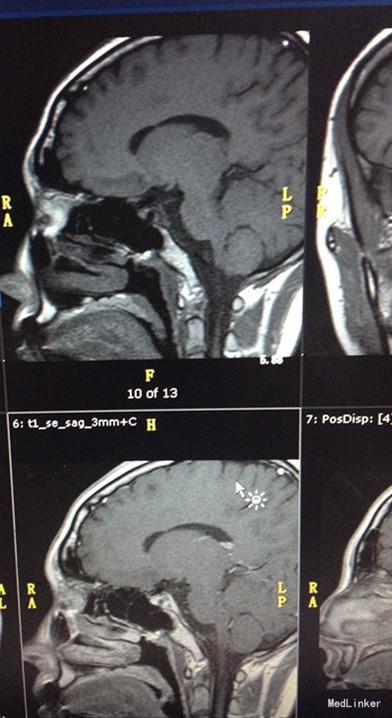

入院查体:无明显异常。 辅助检查:血清泌乳素测定PRL184.00mIU/L。 促性腺激素系列:血清促卵泡刺激素测定FSH0.83mIU/mL,血清促黄体生成素测定LH1.22mIU/mL。 男性激素系列:血清睾酮测定TES2.86nmol/L,血清游离睾酮F-TEST11.79pmol/L,性激素结合球蛋白SHBG72.80nmol/L,血清雄烯二酮测定AND5.53nmol/L,血清脱氢表雄酮及硫酸酯测定DHS6.00umol/L。 雌性激素系列:血清孕酮测定PRG0.77nmol/L,血清雌三醇测定UE3<0.24nmol/L,血清雌二醇测定E2<73.40pmol/L。 妇科超声:子宫附件区未见明显异常回声。垂体增强MR:部分空泡蝶鞍。腰椎骨密度:估量减少。 5日法戈那瑞林兴奋试验: 0分 30分 60分 120分 LH(mIU/mL) 0.11 4.46 4.70 4.41 FSH(mIU/mL) 1.47 3.50 3.93 4.90